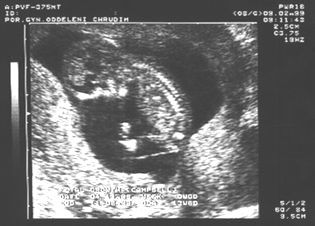

14. týden: páteř plodu

14.týden